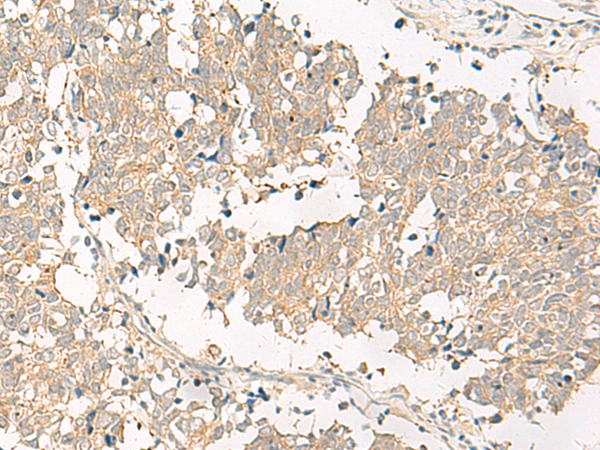

IHC positive control: |

Human lung cancer and Human tonsil |